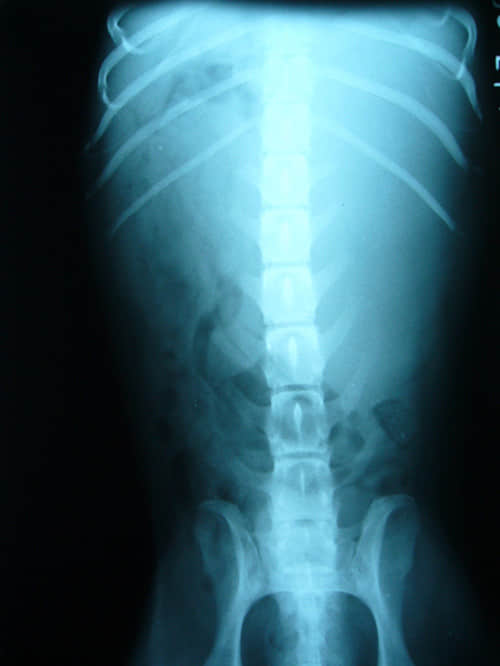

图1、腹背正位平片

图1可以看到,在胃的后侧有一密度均匀的巨大灰色软组织阴影的影像占位,前方与其它组织器官无明显界限,左方紧贴腹壁且界限不清,后方越过第四腰椎,右方侵袭到腰椎右侧,将原有的肠管压迫到腹后侧。